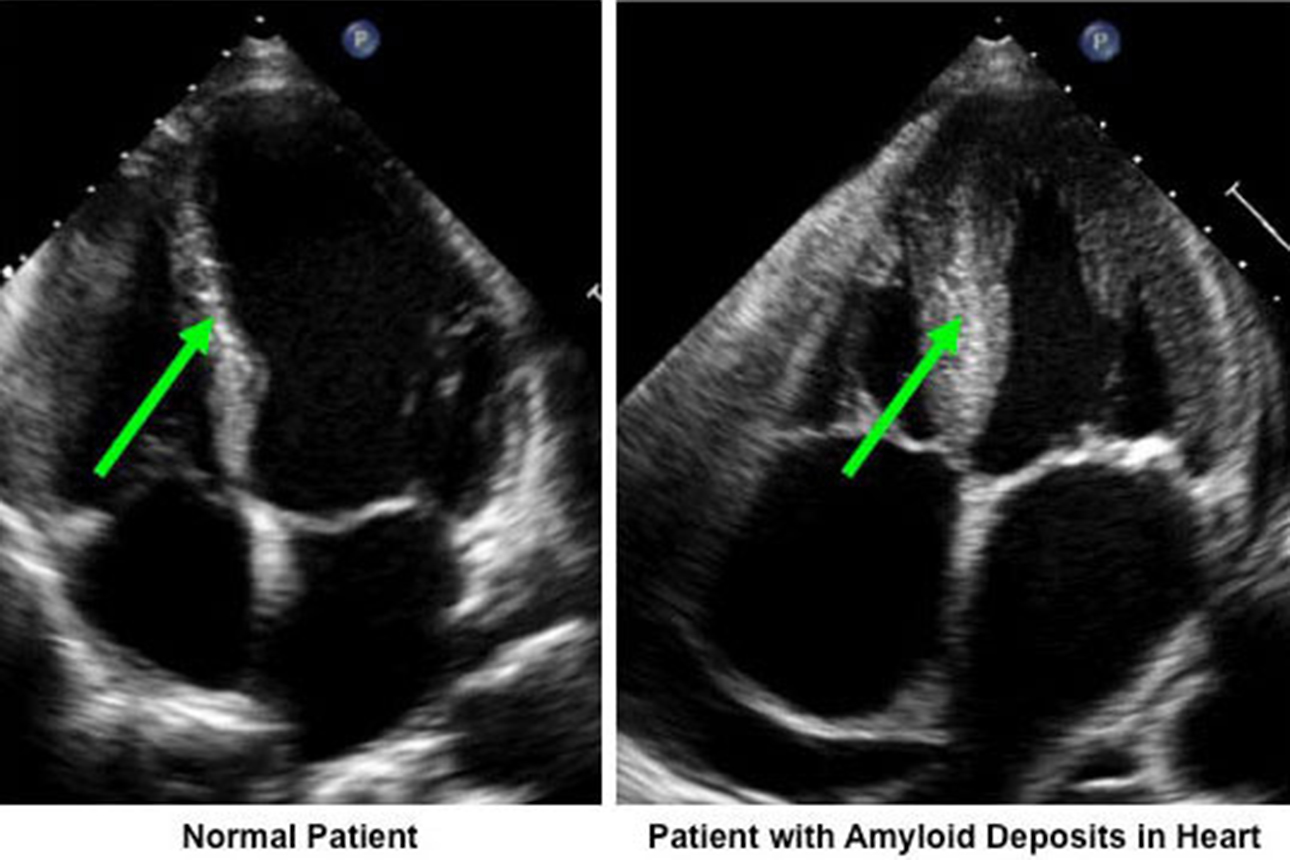

Амилоидоз сердца что это 108 фотографий